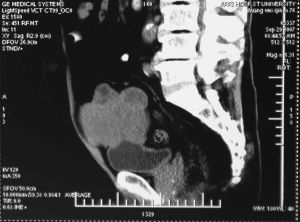

在陰道異物引起的尿瘺中最常見的是膀胱陰道瘺胡建明報導陰道異物致膀胱陰道瘺巨大膀胱結石1例,患者21歲,陰道漏尿6年6年前月經初潮時把一塑膠洗髮精瓶蓋塞入陰道試圖阻止經血外流,之後漸出現尿頻尿急陰道漏尿等。體檢:陰道內見約3cm×3cm塑膠異物瓶蓋口橫穿陰道前壁及膀胱壁埋入膀胱陰道前壁及尿道外口上翻,尿液自瓶蓋旁滲出X線腹部平片示膀胱區見15cm×15cm高密度陰影,診斷:①陰道異物;②膀胱陰道瘺;③膀胱結石在硬膜外阻滯麻醉下行膀胱切開取石及膀胱陰道瘺修補術打開膀胱見黏膜充血水腫,膀胱內見15cm×15cm大結石以瓶蓋為核心形成並堵塞尿道口,術後3周痊癒出院,隨訪4年無異常。

其它輔助檢查:1.X線攝片檢查根據異物性質有時可見不透明陰影